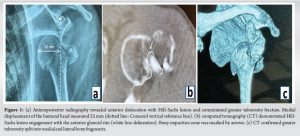

An 83-year-old right-handed female presented to the emergency department with left shoulder pain and deformity. The injury mechanism was confirmed as a ground-level fall. No prior history of shoulder trauma or familial skeletal disorders was documented. Dual-energy X-ray absorptiometry revealed a lumbar spine T-score of −3.1. This value meets the World Health Organization diagnostic criteria for severe osteoporosis. Physical examination revealed pathognomonic squaring deformity of the left shoulder. Complete loss of active motion was observed. Dugas’ sign was confirmed positive. Axillary nerve hypoesthesia was detected in the deltoid dermatome. Deltoid muscle strength was graded 2/5 on the Medical Research Council scale. Intact distal vascular perfusion and radial artery pulsation were documented in the affected upper extremity. Emergency radiographs demonstrated anteroinferior humeral head dislocation. A comminuted greater tuberosity fracture was confirmed. Proximal humeral medial displacement exceeded 25 mm from the coracoid process vertical reference line (Fig. 1a). Closed reduction failed after two attempts. 3D-CT evaluation was subsequently performed.

3D CT confirmed two critical findings: ① Posterolateral Hill-Sachs defects were found interlocked with the anterior glenoid rim (Fig. 1b). ② Coronal plane split fracture of the greater tuberosity was observed, separating into medial and lateral fragments. The medial fragment apex was lodged within the anteroinferior labrum (Fig. 1c). These imaging findings collectively indicated irreducible combined osseous and soft tissue interlocking. Closed reduction was reattempted under general anesthesia. Following an unsuccessful outcome, open surgical intervention was ultimately required. A deltopectoral approach was utilized to expose the surgical field. Direct visualization confirmed two pathological findings: Osseous interlocking between the humeral head and anteroinferior glenoid rim; impacted split fracture fragments of the greater tuberosity. Intraoperative exploration revealed pathognomonic elongation of the LHBT. The distended tendon traversed the humeral head surface, generating dynamic impingement (Fig. 2a). A 2.5-mm Kirschner wire (K-wire) was inserted anterolaterally into the humeral head at 30° angulation. This joystick technique enabled successful disimpaction through counterclockwise rotation combined with gentle inferolateral traction (Fig. 2b). Three high-strength FiberWire® sutures were passed through rotator cuff tendon-bone interfaces. Tension band suture configuration achieved anatomical reduction of comminuted fracture fragments (Fig. 2c). Suture limbs were then secured to pre-designed perforations on Pilos® locking plates. This innovative tendon-bone-plate triple-load fixation construct enabled anatomical restoration while maximally preserving rotator cuff insertion integrity (Fig. 2d). Intraoperative and post-operative radiographs demonstrated complete anatomical reduction of both dislocation and fracture (Fig. 3a and b).